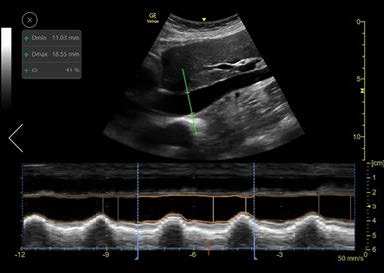

The Auto IVC tool is based on artificial intelligence. We collected thousands of IVC ultrasound images and trained our algorithm to perform the actions required for placing the AMM cursor line through the IVC in precise position (2-3 cm below the diaphragm). The algorithm then measures the maximum and minimum diameters of the IVC throughout a respiratory cycle (Fig.2).

Once the longitudinal view is acquired and the Auto IVC tool is activated, the system automatically locates the IVC and places an AMM cursor through it. The cursor tracks the longitudinal location within the IVC and the AMM automatically adjusts its tilt to maintain perpendicular incidence to the IVC. The user may tap on the image while scanning to choose a different location for the AMM as desired. The Auto IVC tool measures the maximum and minimum diameters of the IVC throughout the respirator cycles in real-time. The AMM timeline traces the diameter of the IVC over time and the collapsibility or distensibility index results are displayed in the measurements result window. Linear graphics on the AMM timeline indicate the minimum and maximum diameters and the user can readjust their positions, if desired, based on clinical judgement.

As the user locates the longitudinal view of the IVC, the system displays a quality indicator cursor to assist with image acquisition. The quality match is represented by the color of the Anatomical M-mode cursor and varies from green to yellow to red to represent ideal/average/unacceptable image presentation.

By default, the timeline is divided into time intervals of 4 seconds each. This is defined as the Calculation Time Interval, or CTI. Results appear in the Results Window for the selected interval. By default, the last complete CTI is selected. If required, the user can select a different CTI. The borders of each CTI are marked by dotted lines. Calculations are done in real time and the results are displayed in the results box upon completion of each respiratory cycle. The image is stored, and the results are saved in the measurements report.

Figure 2: Auto IVC Tool Screen layout